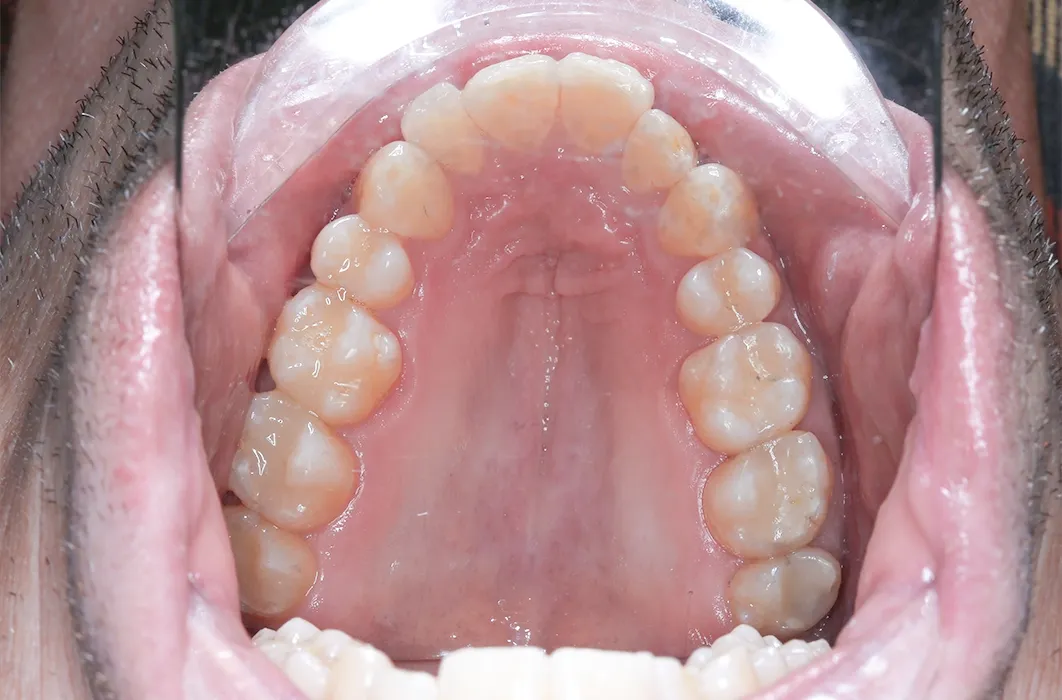

The results

Mr C’s teeth went from being worn, darkened, and at risk of breakdown to looking healthier, stronger, and natural. The resin restorations not only gave his smile a more uniform appearance, but also reinforced surfaces to reduce the risk of future decay and damage.

This case highlights the importance of timely management of worn and decayed teeth. Each patient’s situation is unique, and treatment needs and outcomes will vary, but in this example composite resin fillings were used to:

- Remove areas of decay and replace older amalgam (metal) restorations

- Provide structural support to the affected teeth

- Create a tooth-coloured surface that blends with surrounding teeth

- Maintain the existing teeth in function

In Mr C’s case, composite resin restorations were placed to manage decay and replace older amalgam fillings. This approach provided stability for the affected teeth and maintained them in function.